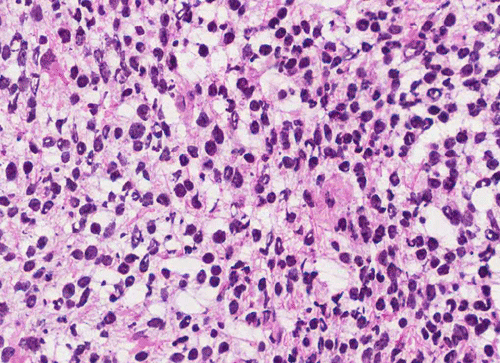

Frozen

Pathology of the Case: The tumor is composed of neoplastic small blue cells on the cytologic preparation (Pancel C and D) with only minimal amount of cytoplasm. On frozen section (Panel E and F), the tumor cells are packed in solid sheets without specific pattern of arrangement. On permanent sections, the tumor again is composed of solid sheets of small blue cell tumors with rather monotonous nuclei (Panel G and H). In some areas, there is some small neuropil islands (Panel I). No distinct perivascular coronary arrangement is noted.  (Panel J). There is a moderate labeling index on Ki67 (Panel K). The tumor cells are strongly positive for neurofilament proteins (Panel L). Some large stellate, cells positive for glial fibrillary acidic protein (GFAP) are also present and these cells may represent reactive astrocytes (Panel M).